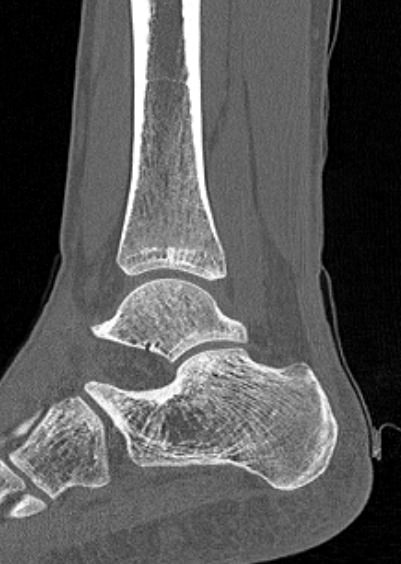

Во время исследования рентгеновская трубка томографа вращается вокруг исследуемой области и производит множество послойных снимков с шагом от 0,5 мм. Полученные снимки поперечного сечения с помощью компьютерной программы могут быть преобразованы в 3D-изображения исследуемого органа. Это позволяет выявлять различные патологические процессы на начальных стадиях и назначать своевременное лечение.

За счет быстроты, доступности и неинвазивности (то есть исследование не требует вмешательства в организм) метод КТ особенно востребован в ортопедии и травматологии. Мультиспиральная КТ лучше всего визуализирует плотные ткани, такие как кости и хрящи. Поэтому, в первую очередь, применяется для диагностики травм суставов (вывихов, подвывихов, переломов).

В отличие от обычного рентгена, при котором изображения костных структур накладываются друг на друга, что затрудняет диагностику, компьютерная томография дает возможность увидеть объемную модель сустава, наглядно оценить пространственное соотношение внутрисуставных структур, суставных поверхностей, расположение костных отломков при переломах и травмах. Это особенно важно в ходе подготовки к оперативному вмешательству и в послеоперационном периоде для оценки успешности проведенной операции.